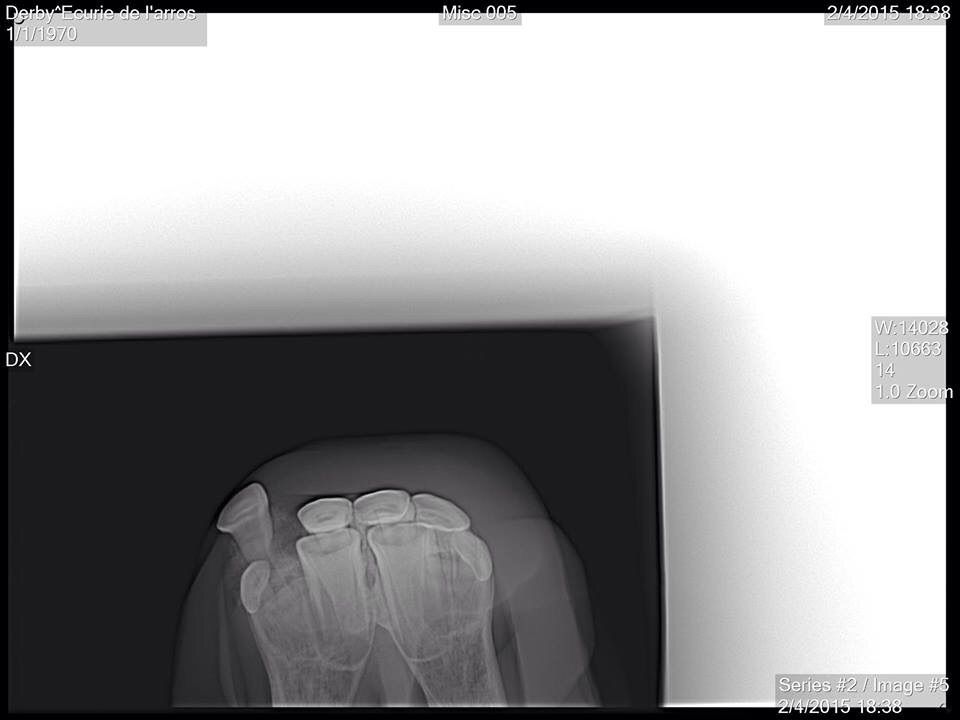

| Dire merci | Tout d abord desolee de ne pas vous avoir donné des nouvelles plus tôt . Le loulou va parfaitement bien, la dent etait bien fracturée, un cerclage a été réalise par l ecole veto de Nantes. Il est resté en place 6 semaines avant d être enlevé. Aujourdhui il est de nouveau au pré avec ses copains et tout va pour le mieux pour lui. Voici quelques photos: ![]() [/url] |

Par playboy78 : le 22/04/15 à 14:03:05

| Dire merci | ![]() [/url] ![]() [/url] ![]() [/url] ![]() [/url] ![]() [/url] |

| Dire merci | Et une fois le cerclage réalisé, l intervention a duré 2 bonnes heures, le chirurgien a beaucoup gratté la gencive pour pouvoir remettre la dent à sa place. Le travail realisé est vraiment superbe, on ne se rend aujourdhui quasiment plus compte de ce qui lui est arrivé.![]() [/url] |